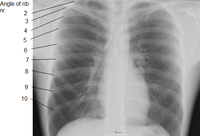

Humans have 24 ribs (12 pairs). The first seven sets of ribs, known as "true ribs" (costae verae) also known as vertebrosternal ribs, are directly attached to the sternum through the costal cartilage. Rib 1 is unique and harder to distinguish than other ribs. It is a short, flat, C-shaped bone. The vertebral attachment can be found just below the neck and the majority of this bone can be found above the level of the clavicle. Ribs 2 through 7 have a more traditional appearance and become longer and less curved as they progress downwards.[1] The following five sets are known as "false ribs" (costae spuriae), three of these sharing a common cartilaginous connection to the sternum, while the last two (eleventh and twelfth ribs) are termed floating ribs (costae fluctuantes) or vertebral ribs. They are attached to the vertebrae only, and not to the sternum or cartilage coming off of the sternum. Some people lack one of the two pairs of floating ribs, while others have a third pair.

In general, human ribs increase in length from ribs 1 through 7 and decrease in length again through rib 12. Along with this change in size, the ribs become progressively oblique (slanted) from ribs 1 through 9, then less slanted through rib 12.[1]